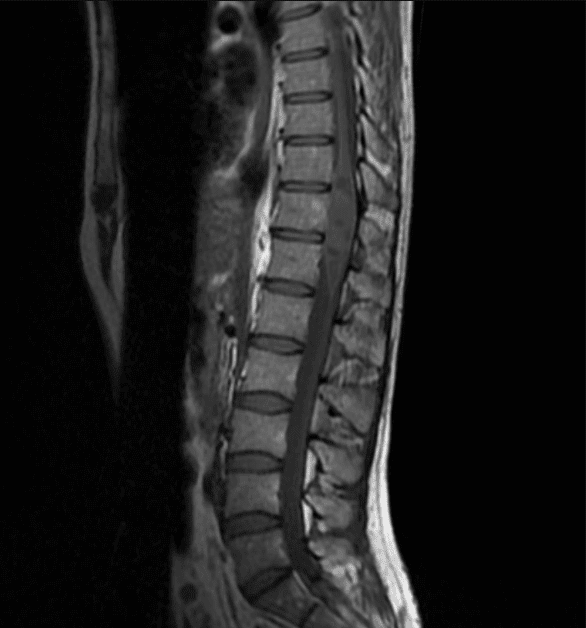

U màng nội tủy

» Thông tin: Nữ giới – 35 tuổi.

» Lâm sàng: Yếu chi dưới.

# U màng nội tủy nhầy nhú (Myxopapillary Ependymoma).